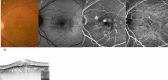

This multicenter study aimed to assess the short-term effectiveness and safety of faricimab in treatment-naïve patients with wet age-related macular degeneration (wAMD) in Japan. We retrospectively reviewed 63 eyes of 61 patients with wAMD, including types 1, 2, and 3 macular neovascularization as well as polypoidal choroidal vasculopathy (PCV). Patients received three consecutive monthly intravitreal injections of faricimab as loading therapy. Over these 3 months, visual acuity improved gradually compared to baseline. Moreover, the central foveal thickness decreased significantly at 1, 2, and 3 months compared to baseline (p < 0.0001). At 3 months after initiation of faricimab therapy, a dry macula (defined as absence of intraretinal or subretinal fluid) was achieved in 82% of the eyes. Complete regression of polypoidal lesions was observed in 52% of eyes with PCV. Subfoveal choroidal thickness also decreased significantly at 1, 2, and 3 months compared to baseline (p < 0.0001). Although retinal pigment epithelium tears developed in two eyes, there were no other ocular or systemic complications observed during the 3 months of loading therapy. In conclusion, loading therapy using faricimab resulted in improved visual acuity and retinal morphology in Japanese patients with wAMD without particular safety issues.